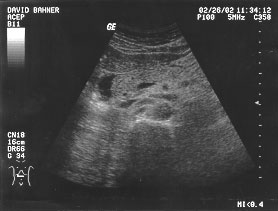

Aorta - renal (unlabeled)